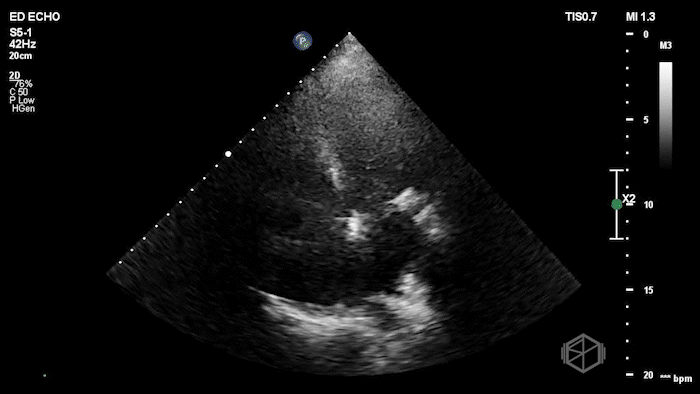

Here is the POCUS:

The POCUS shows a probably borderline LV systolic function. There is significant mitral valve calcification present. There is a mobile echodensity present near the mitral valve. On the color doppler there is severe mitral regurgitation.

In the ED, markedly elevated troponin (~42,000) and BNP 1520. Cardiology TTE revealed a 1.4 × 0.7 cm mobile echodensity on the mitral valve, concerning for papillary muscle or chordal rupture, with differential also including flail leaflet vs. vegetation, in the setting of wall motion abnormalities. The patient had a cath that showed severe triple-vessel CAD, prompting IABP placement and ICU admission. TEE confirmed severe MR due to chordal rupture with preserved LV function. She eventually did get a mitral valve replacement, but had a complex course and ultimately was made comfort care.

Diagnosis: Chordal rupture, acute severe mitral regurgitation